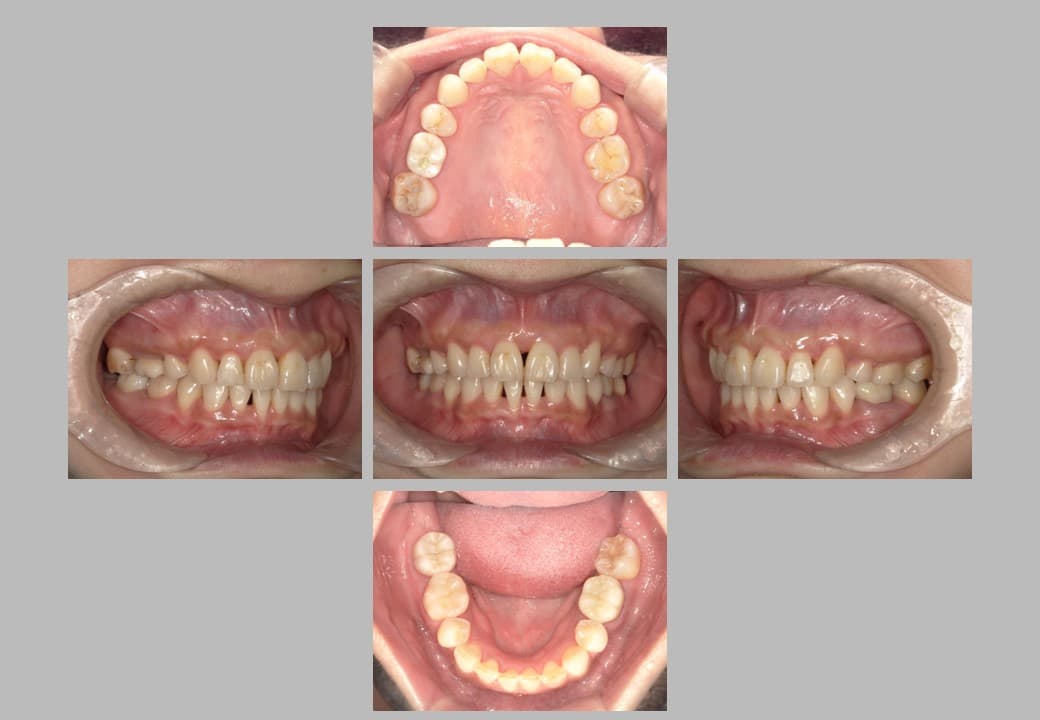

• 治療後